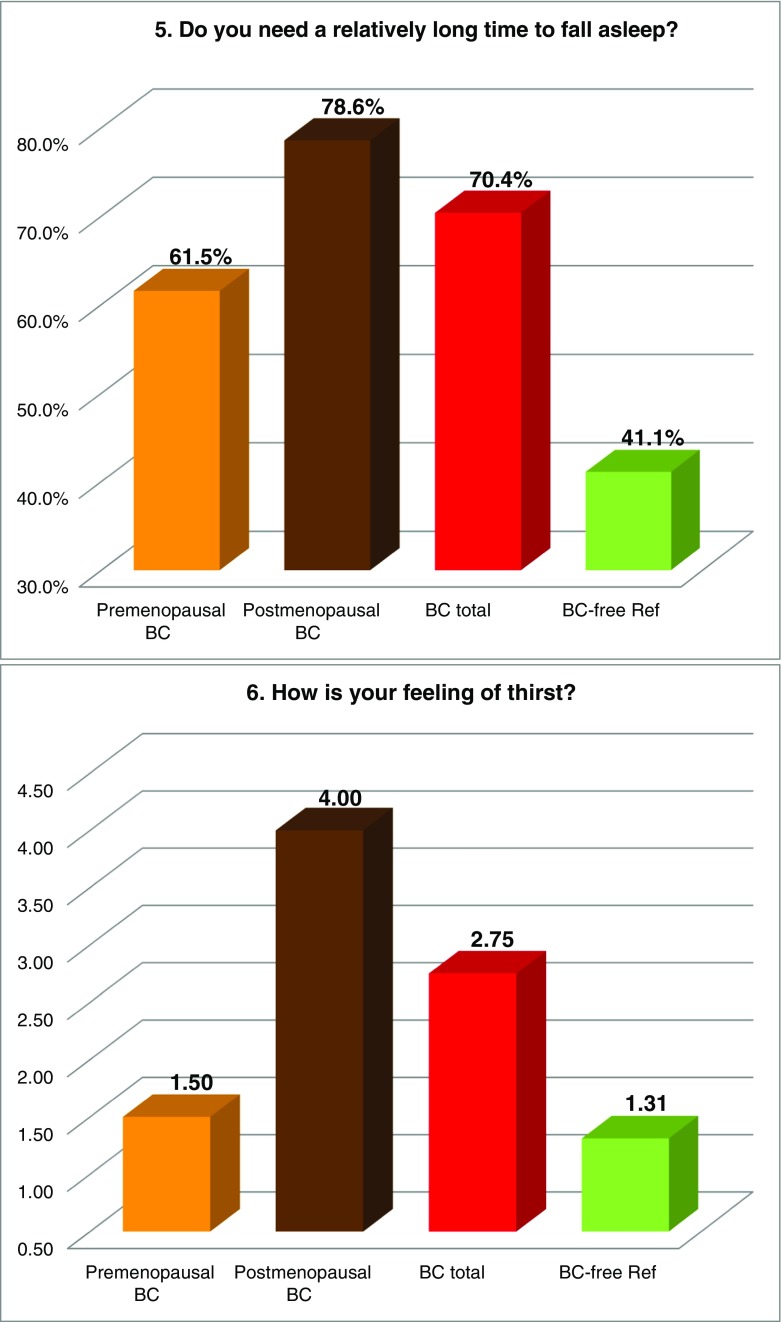

FS prevalence evaluated by individual symptoms

Figure 2 summarises the prevalence of individual “Flammer Syndrome” symptoms (1–15) in two main groups of comparison—“BC total” patients versus the reference group of “BC-free” individuals as well as in individual subgroups of BC patients subdivided according to their menopausal status. Higher prevalence in “BC total” (marked in red) has been demonstrated for all 15 symptoms investigated in this study. Statistical significance has been recorded for symptoms 1 (cold extremities), 2 (feeling cold), 5 (prolonged sleep onset), 7 (headache), 8 (accompanying symptoms), 9 (drug sensitivity) and 11 (smell perception); corresponding p values are provided in Table 3. Although being statistically non-significant (p = 0.103), a substantially greater prevalence has been demonstrated for symptom 6: “no feeling of thirst and drinking too little” the BC patients, in general, have demonstrated two times more frequently compared to the disease-free reference group; for the postmenopausal BC, this difference was even more pronounced. Also, the appearance of tinnitus (symptom 14), although being statistically non-significant (p = 0.095), was evidently more frequent in BC, particularly in the premenopausal subgroup demonstrating about two times higher prevalence compared to the disease-free reference group. Symptom 3 (low blood pressure) was more specific for the premenopausal BC demonstrating 22% higher prevalence against the disease-free reference group. In contrast, symptom 12 (low body weight in early adulthood) was more specific for postmenopausal BC. A slightly higher prevalence was demonstrated for symptom 4 (dizziness) in BC. Strong plurality has been demonstrated amongst the BC subgroups for the following three symptoms: 10 (pain, more specific for the postmenopausal BC), 13 (perfectionism, more specific for the postmenopausal BC) and 15 (skin blotches in stress, more specific for the premenopausal BC) as summarised in Table 3.

Fig. 2.

Evaluation of the prevalence of individual symptoms (1–15) of the “Flammer Syndrome” phenotype in two groups of comparison: “Breast cancer diseased” (BC total) versus “Breast cancer-free” reference (BC-free Ref) groups. Therein, the entire breast cancer patient pool (“BC total”) has been additionally analysed in subgroups stratified according to the menopausal status of the patients. For more details regarding the patient’s recruitment and stratification, see “Materials and methods” section. The prevalence in each individual group is presented by percentage of individuals who have responded to the corresponding question with “frequently” and “sometimes” pooled together. Responders answering with “I do not know” have been excluded from the overall numbers/calculations. Question-specific notes: question 6—the ratio between “I do not feel thirsty and drink little” and “I feel much thirsty and drink a lot” has been calculated and expressed as X times; question 12—answers “very slim” and “slim” are pooled together and presented in percentage

Table 3.

Symptoms of the “Flammer Syndrome” recorded in “Metastatic breast cancer patients” versus “Breast cancer-free individuals” groups of comparison

The table summarises the results demonstrated in Fig. 2; the following system is employed: “+” means higher prevalence of the corresponding symptom (above the lowest average of the groups of comparison); “−“ means lower prevalence of the corresponding symptom (lowest average and below it); “++“ means values sufficiently over the highest average. All 15 symptoms demonstrate increased prevalence in BC total versus BC-free. The level of significance is noted: p values below 0.05 are considered statistically significant and marked in red colour (symptoms 1, 2, 5, 7, 8, 9, 11). Thirteen symptoms united within the green-marked cluster demonstrate the prevalence ultimately increased in BC total as well as BC subgroups. Although the prevalence of symptoms 13 and 15 (yellow-marked cluster) is slightly increased in “BC total” compared to “BC-free,” it varies in BC subgroups demonstrating a particularly strong plurality amongst the patients with the metastatic BC investigated in the current study

The meaning of individual FS symptoms specifically for the BC patient cohort has been discussed in detail in the recently published article “Breast Cancer and Flammer Syndrome: Any Symptoms in Common for Prediction, Prevention and Personalised Medical Approach?” [28]. Current chapter emphasises a particular relevance of the FS symptoms for the metastatic disease in the BC patient cohort: all 15 symptoms demonstrate the prevalence in the metastatic BC versus BC-free reference group with a statistical significance (p ≤ 0.05) for seven symptoms as summarised in Table 3. Other symptoms, even being statistically non-significantly prevalent within this study, can be of great importance for the BC pathology and metastatic disease. Hence, symptom 3 (low blood pressure, p = 0.127) is particularly relevant for the premenopausal subgroup and may strongly contribute the cardio-vascular component characteristic for the FS as explained above. Another example is the following: symptom 4 (dizziness, p = 0.762) has been described earlier as being permanently present and stepwise worsening in BC followed by metastasis in the brain [20, 33]. Finally, the normal feeling of thirst (symptom 6, p = 0.103) is extremely important and if diminished (here two times in BC versus BC-free) plays a crucial role in the body dehydration and BC development [20].